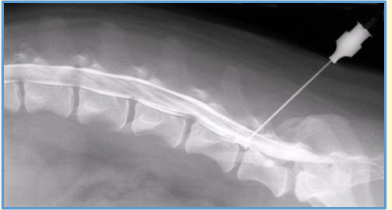

Myelography involves ..

An injection of a contrast agent into the subarachnoid space to highlight the spinal cord

Where can it be injected?

Site for cisternal puncture

Site for Lumbar puncture

The cisternal magna at the base of the skull

Lumbar spinal canal, usually at L3-4 or L4-5